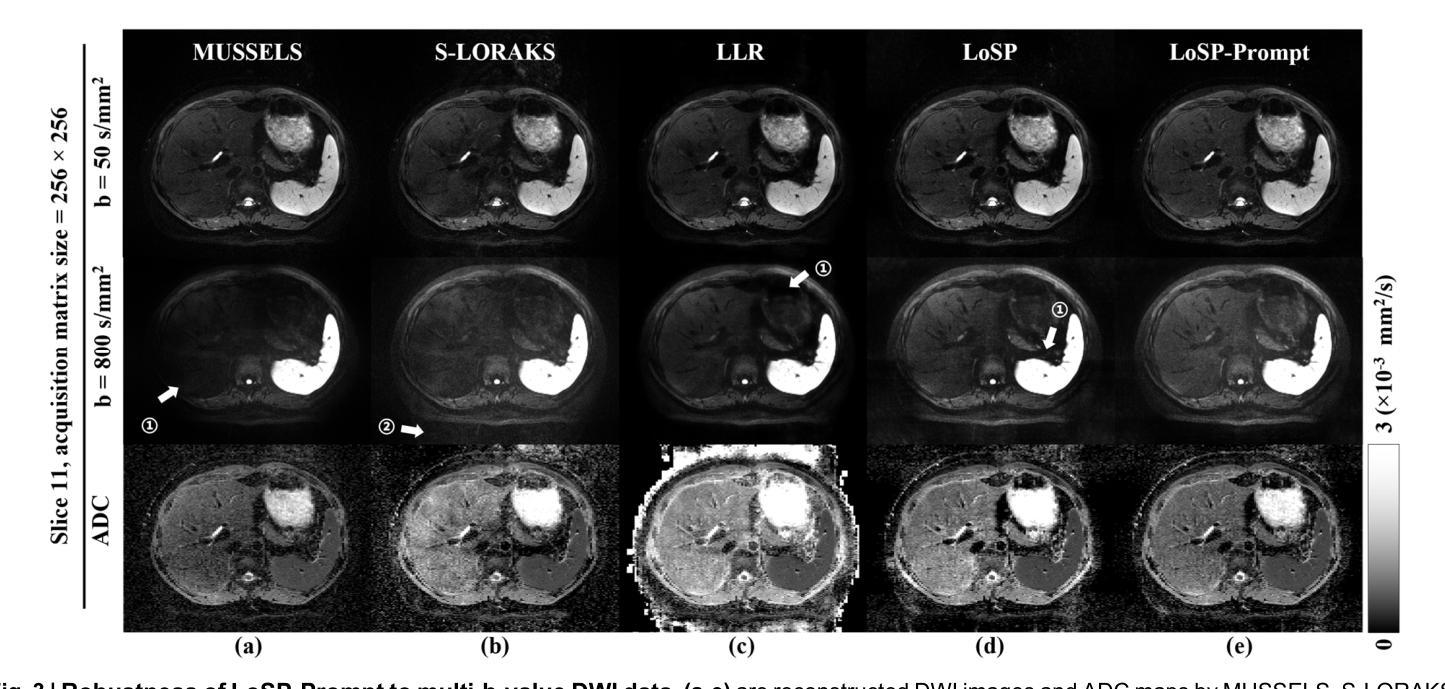

Clinical adoption of multi-shot diffusion-weighted magnetic resonance imaging (multi-shot DWI) for body-wide tumor diagnostics is limited by severe motion-induced phase artifacts from respiration, peristalsis, and so on, compounded by multi-organ, multi-slice, multi-direction and multi-b-value complexities. Here, we introduce a reconstruction framework, LoSP-Prompt, that overcomes these challenges through physics-informed modeling and synthetic-data-driven prompt learning. We model inter-shot phase variations as a high-order Locally Smooth Phase (LoSP), integrated into a low-rank Hankel matrix reconstruction. Crucially, the algorithm’s rank parameter is automatically set via prompt learning trained exclusively on synthetic abdominal DWI data emulating physiological motion. Validated across 10,000+ clinical images (43 subjects, 4 scanner models, 5 centers), LoSP-Prompt: (1) Achieved twice the spatial resolution of clinical single-shot DWI, enhancing liver lesion conspicuity; (2) Generalized to seven diverse anatomical regions (liver, kidney, sacroiliac, pelvis, knee, spinal cord, brain) with a single model; (3) Outperformed state-of-the-art methods in image quality, artifact suppression, and noise reduction (11 radiologists’ evaluations on a 5-point scale, $p<0.05$), achieving 4-5 points (excellent) on kidney DWI, 4 points (good to excellent) on liver, sacroiliac and spinal cord DWI, and 3-4 points (good) on knee and tumor brain. The approach eliminates navigator signals and realistic data supervision, providing an interpretable, robust solution for high-resolution multi-organ multi-shot DWI. Its scanner-agnostic performance signifies transformative potential for precision oncology.

在临床采用多回扩散加权磁共振成像(multi-shot DWI)进行全身肿瘤诊断时,受到呼吸、蠕动等引起的严重运动相位伪影的限制,再加上多器官、多切片、多方向和多b值的复杂性。在这里,我们引入了一种重建框架,名为LoSP-Prompt,它通过物理信息建模和合成数据驱动提示学习来克服这些挑战。我们将不同射击之间的相位变化建模为高阶局部平滑相位(LoSP),并将其集成到低秩Hankel矩阵重建中。关键的是,该算法的秩参数是通过仅使用模拟生理运动的合成腹部DWI数据进行提示学习来自动设置的。在超过10,000张临床图像(43名受试者,4种扫描仪型号,5个中心)的验证中,LoSP-Prompt:(1)实现了临床单发DWI两倍的空间分辨率,提高了肝脏病变的清晰度;(2)使用单一模型推广到七个不同的解剖区域(肝脏、肾脏、骨盆、膝盖、脊髓、大脑);(3)在图像质量、伪影抑制和降噪方面优于最新方法(11名放射科医生在五点量表上进行评估,p<0.05),在肾脏DWI上获得4-5分(优秀),肝脏、骨盆和脊髓DWI上获得4分(良好至优秀),膝盖和肿瘤大脑获得3-4分(良好)。该方法消除了导航信号和真实数据监督,提供了一种可解释、稳健的解决方案,用于高分辨率多器官多回DWI。其扫描仪无关的性能表明对精准肿瘤学具有变革潜力。

Summary

在医学图像领域中,针对体部肿瘤的诊断采用了多站式扩散加权磁共振成像(multi-shot DWI),但由于呼吸、蠕动等引起的严重运动引起的相位伪影限制了其临床应用。为解决此问题,本文提出了一种重建框架LoSP-Prompt,通过物理信息建模和合成数据驱动的提示学习来克服这些挑战。该算法实现了临床单站式DWI的两倍空间分辨率,提高了肝脏病变的辨识度,并在多个解剖区域具有广泛应用性。此外,其在图像质量、伪影抑制和降噪方面均优于现有技术,并在肾脏DWI上取得了卓越表现。此方法无需导航信号和真实数据监督,提供了一种可解释、稳健的高分辨率多站式DWI解决方案,对精确肿瘤学具有变革潜力。

Key Takeaways

1. 多站式扩散加权磁共振成像(multi-shot DWI)在临床应用中受到限制,主要由于运动引起的相位伪影。

2. 提出了一种重建框架LoSP-Prompt,通过物理信息建模和合成数据驱动的提示学习来解决挑战。

3. LoSP-Prompt实现了两倍于临床单站式DWI的空间分辨率,提高了肝脏病变的辨识度。

4. 该方法可在多个解剖区域广泛应用,包括肝脏、肾脏、骨盆、膝盖、脊髓和大脑。

5. LoSP-Prompt在图像质量、伪影抑制和降噪方面表现出卓越性能,优于现有技术。

6. 该方法无需导航信号和真实数据监督,提供了可解释性和稳健性。